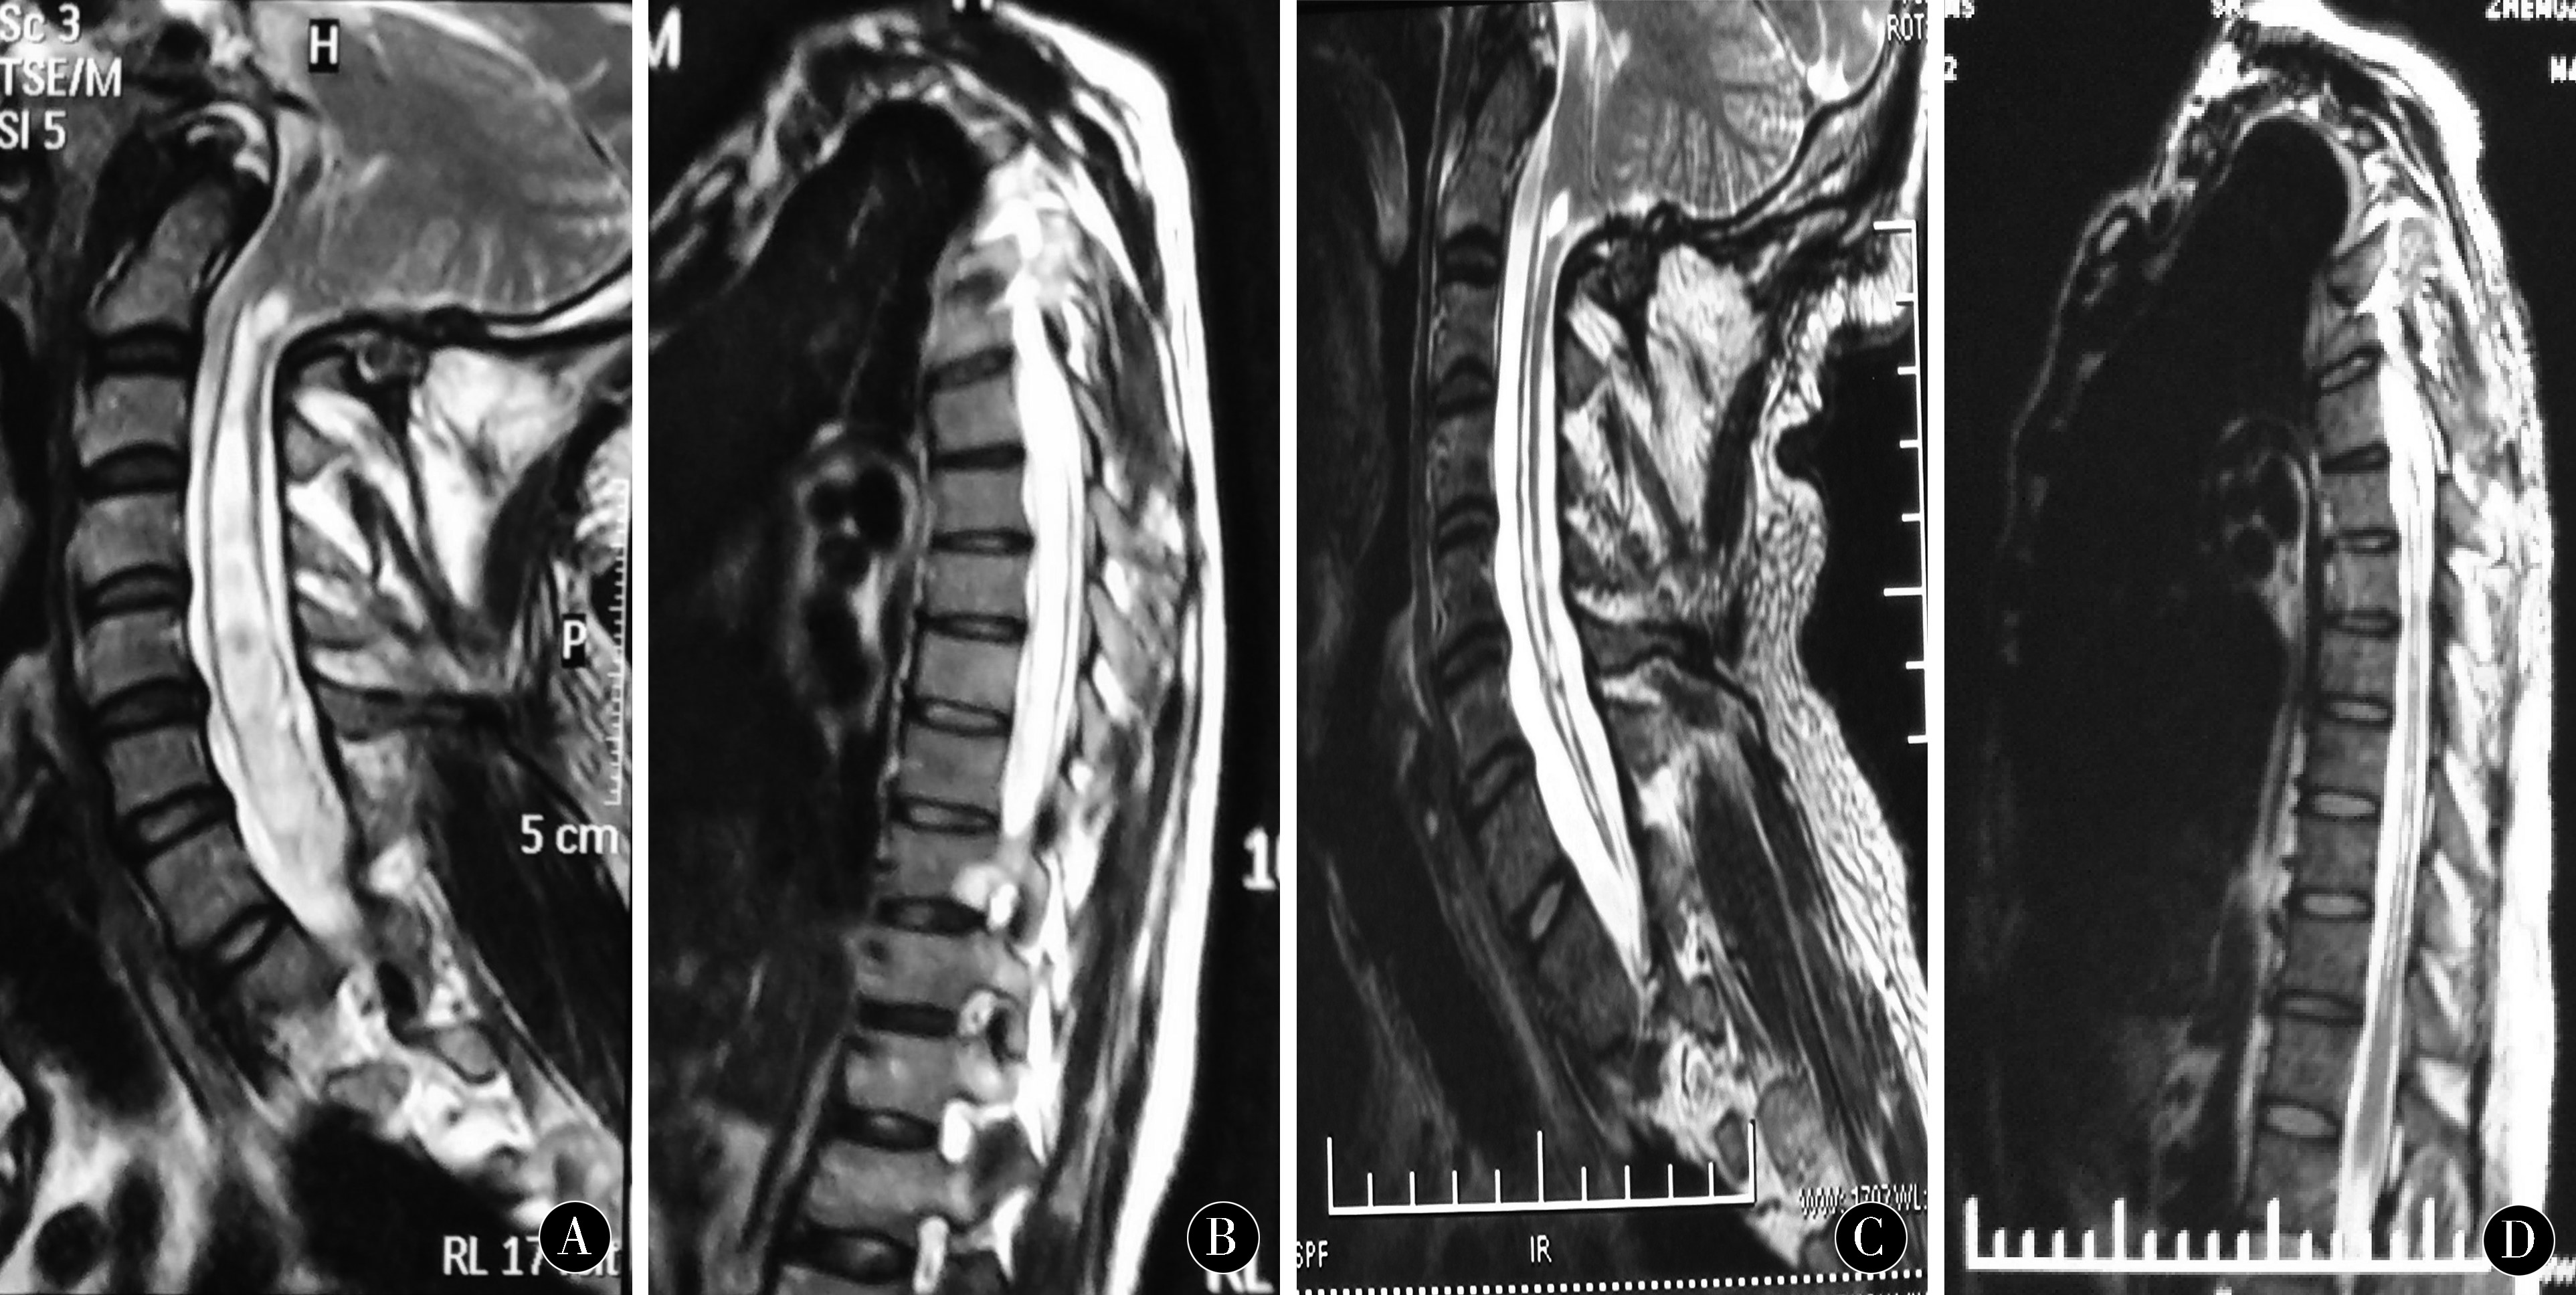

本组19例患者随访3月~2 a,临床症状有不同程度改善,明显改善14例,稳定4例,临床症状进行性加重并出现新的神经症状1例。全部患者未出现死亡、胸腔积液及感染。1例患者术后症状明显改善,3个月后症状进行性加重,复查MRI提示空洞无明显变化,再次手术探查发现分流管T端炎性粘连梗阻,调整分流管后,症状改善。术后MRI复查空洞缩小80%至完全消失15例(见图1),空洞缩小50%~80%3例,空洞缩小50%以下1例。19例患者电话或门诊随访,mJOA评分(13±2.4)分,进行统计学分析,采用非参数秩和检验法,结果显示P<0.001。

图1 患者:49岁,男性,四肢麻木无力并痛温觉减退5 a,加重1个月。4 a前在外院行后颅窝减压,效果欠佳。A、B:患者术前MRI检查提示:颈胸段脊髓中央管扩张,脊髓变薄,脊髓空洞。C、D:患者术后1周复查MRI检查提示:脊髓空洞明显缩小,患者症状明显改善

Figure 1 49 years oldmalelimb numbnessweakness and pain and temperature depression 5 Aaggravating 1 months.4 the decompression of posterior fossa in the external hospital was not effective before a.Preoperative MRI examination in a and B patients suggested that the central canal of the cervical and thoracic spinal cord was dilatedthe spinal cord became thinner and the spinal cord cavity.The MRI examination of C and D patients 1 weeks after operation showed that the cavity of the spinal cord was obviously reduced.The patient's symptoms improved significantly